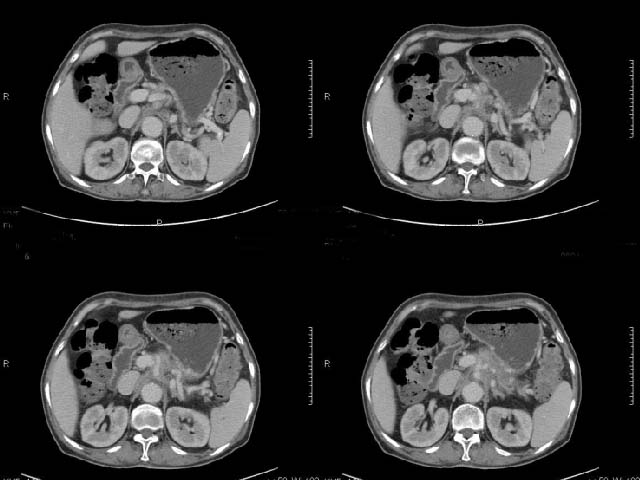

女,69岁,浑身乏力,腹泻半年余,无腹疼,排泄物中含有脂肪球,抗炎治疗一周仍不缓解,来我院检查发现明显低钾血症,给予补钾(氯化钾)一周后,血钾恢复正常,经化验检查,尿钾持续明显高于正常,临床考虑患者不仅消化道失钾,还伴有泌尿系统失钾,故进行ct增强检查看肾上腺是否有病变。ct表现为胰腺肥大,而且体尾部强化较弱,明显呈稍低密度,胰尾见有更低密度,而且胰腺与周围组织的脂肪间隙不清,大血管周围似乎有包绕现象,患者是否有过胰腺炎病史,家属说不清楚;而双侧肾上腺大小形态,本人认为未见异常,本人倾向于考虑:慢性胰腺炎伴假性囊肿,不排除胰腺占位可能;但是不知怎么解释持续尿钾现象。请大家发表高见!